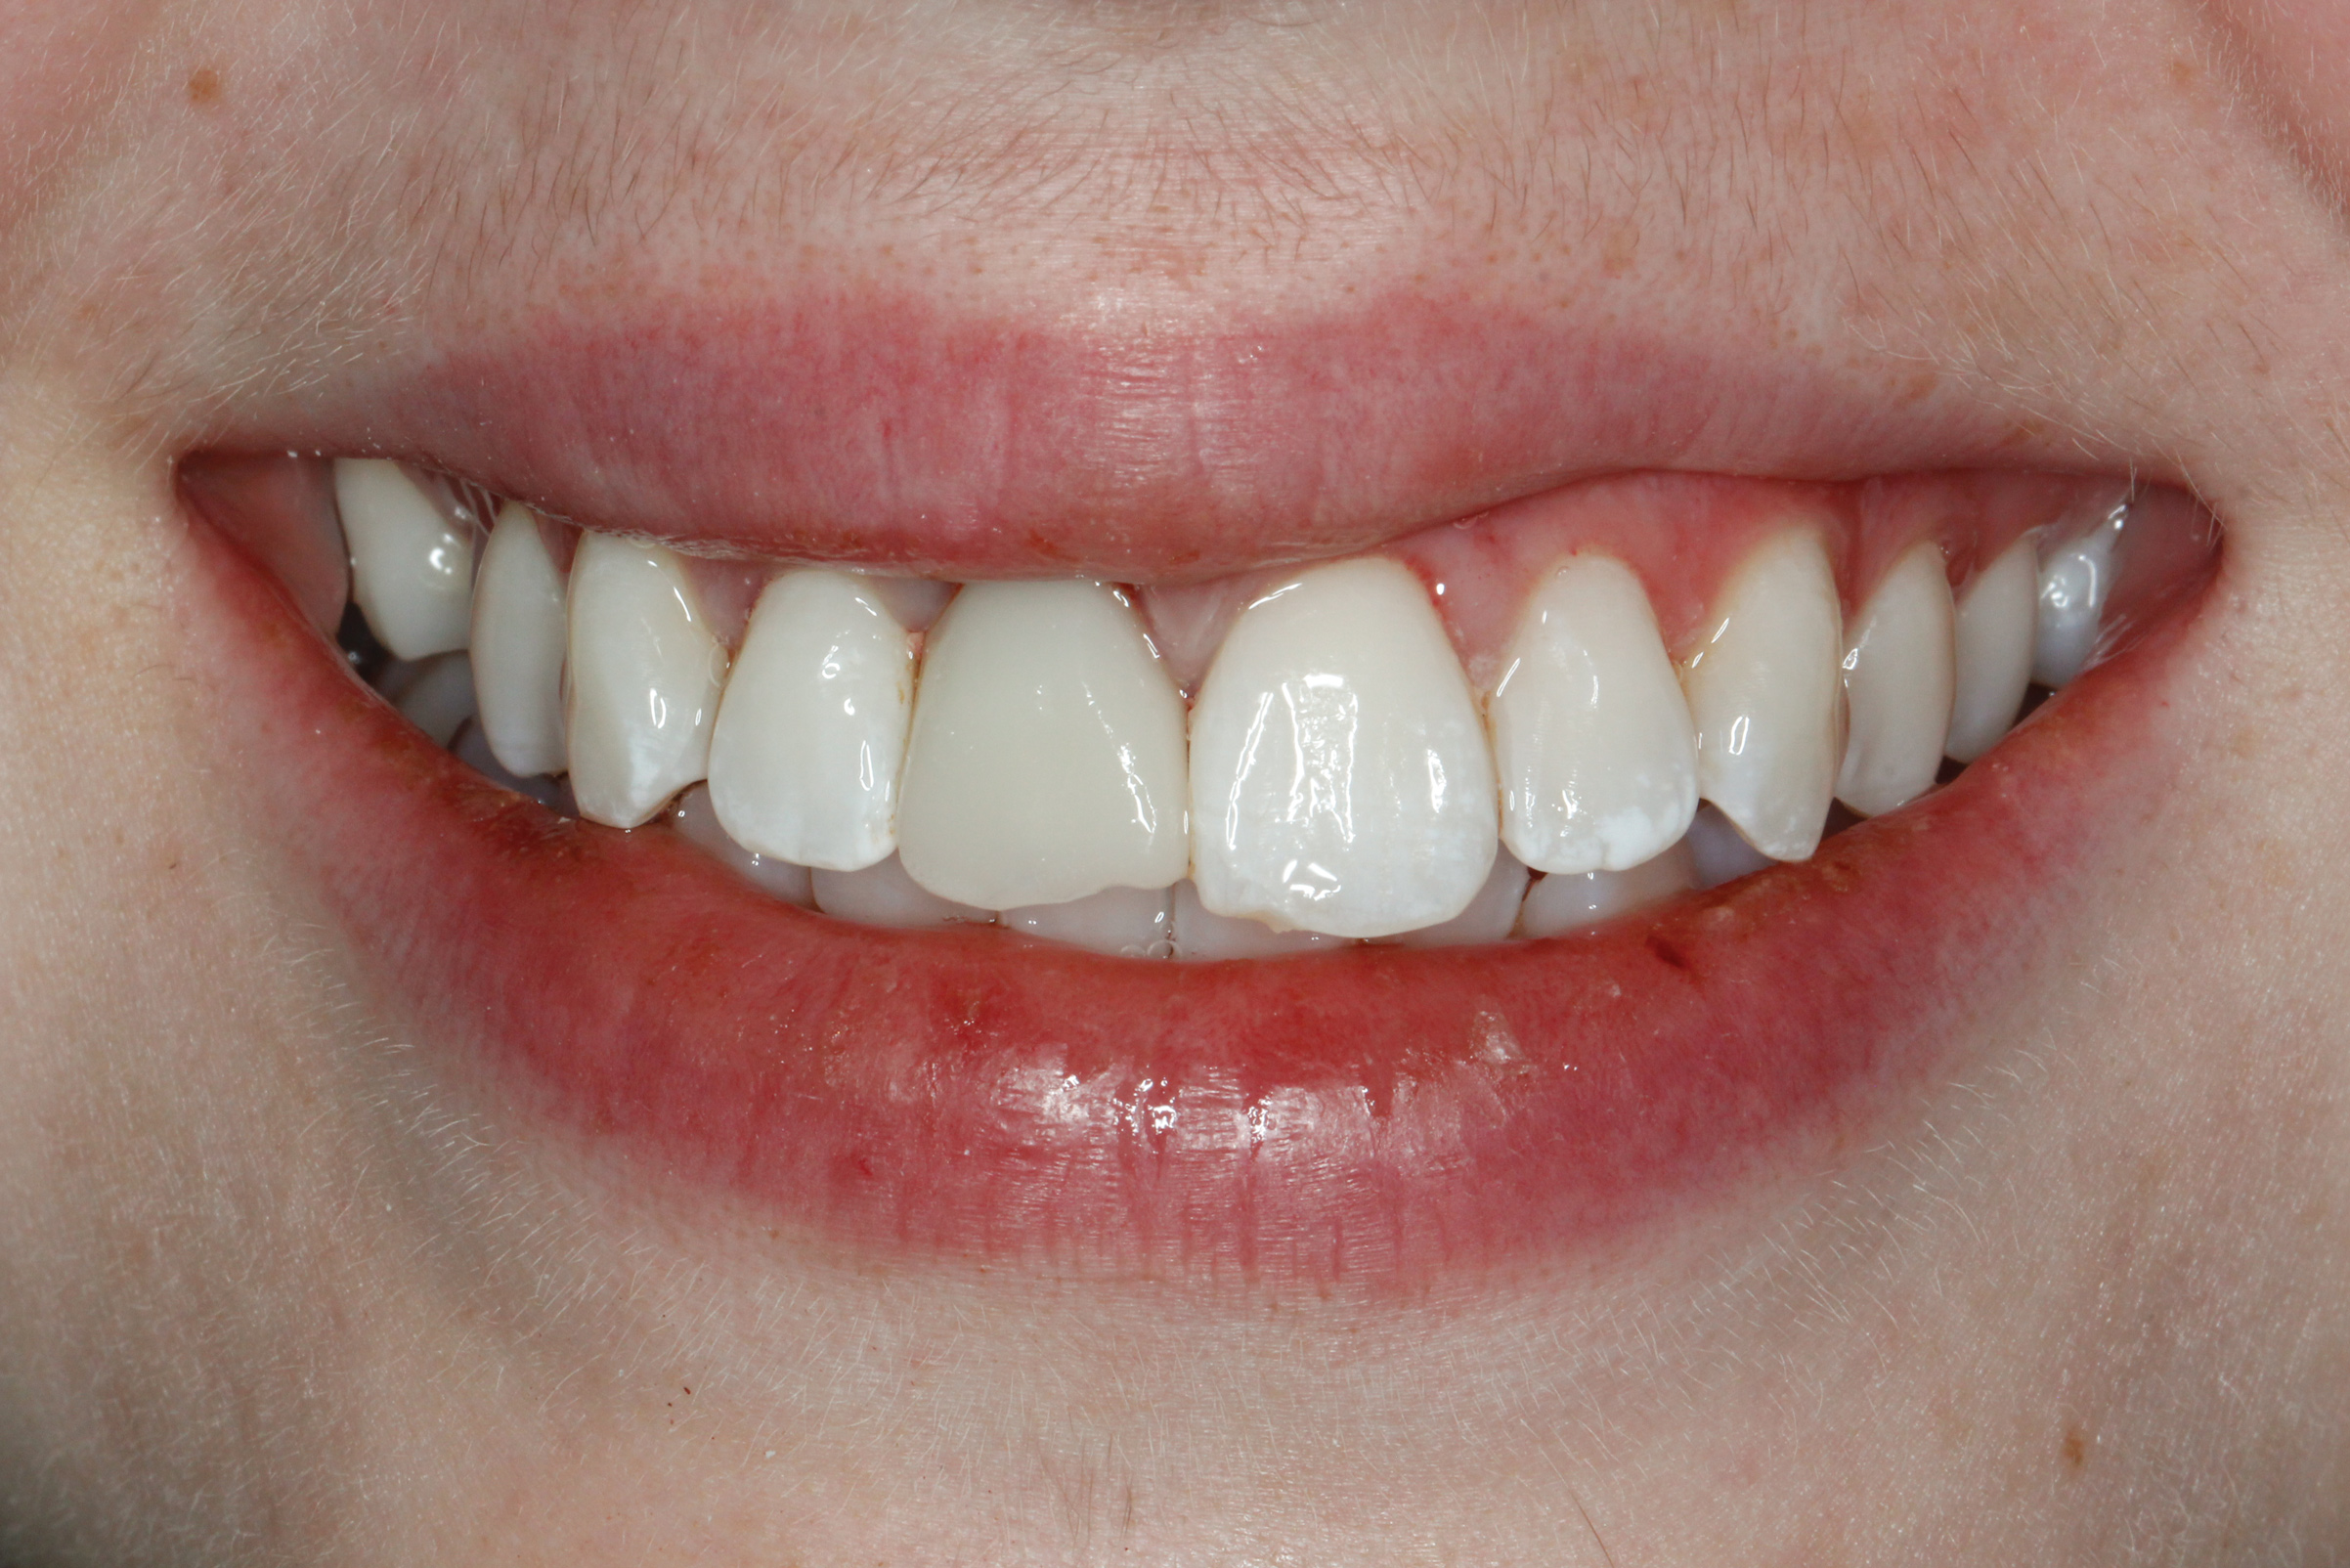

Fig 8. Preoperative intraoral photograph. Full-arch restoration was mobile and unesthetic.

Figure 8